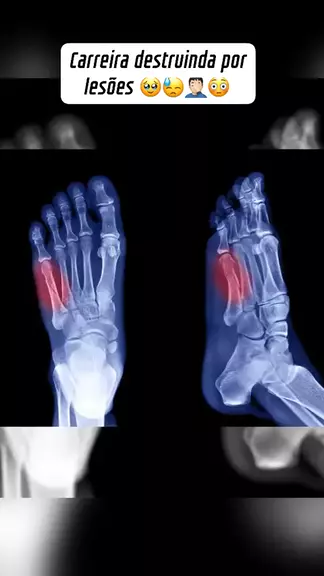

Carreira destruinda por lesões 🥹😓🤦🏻‍♂️😳#lesoes #futebol #tragedia #esporteviral More